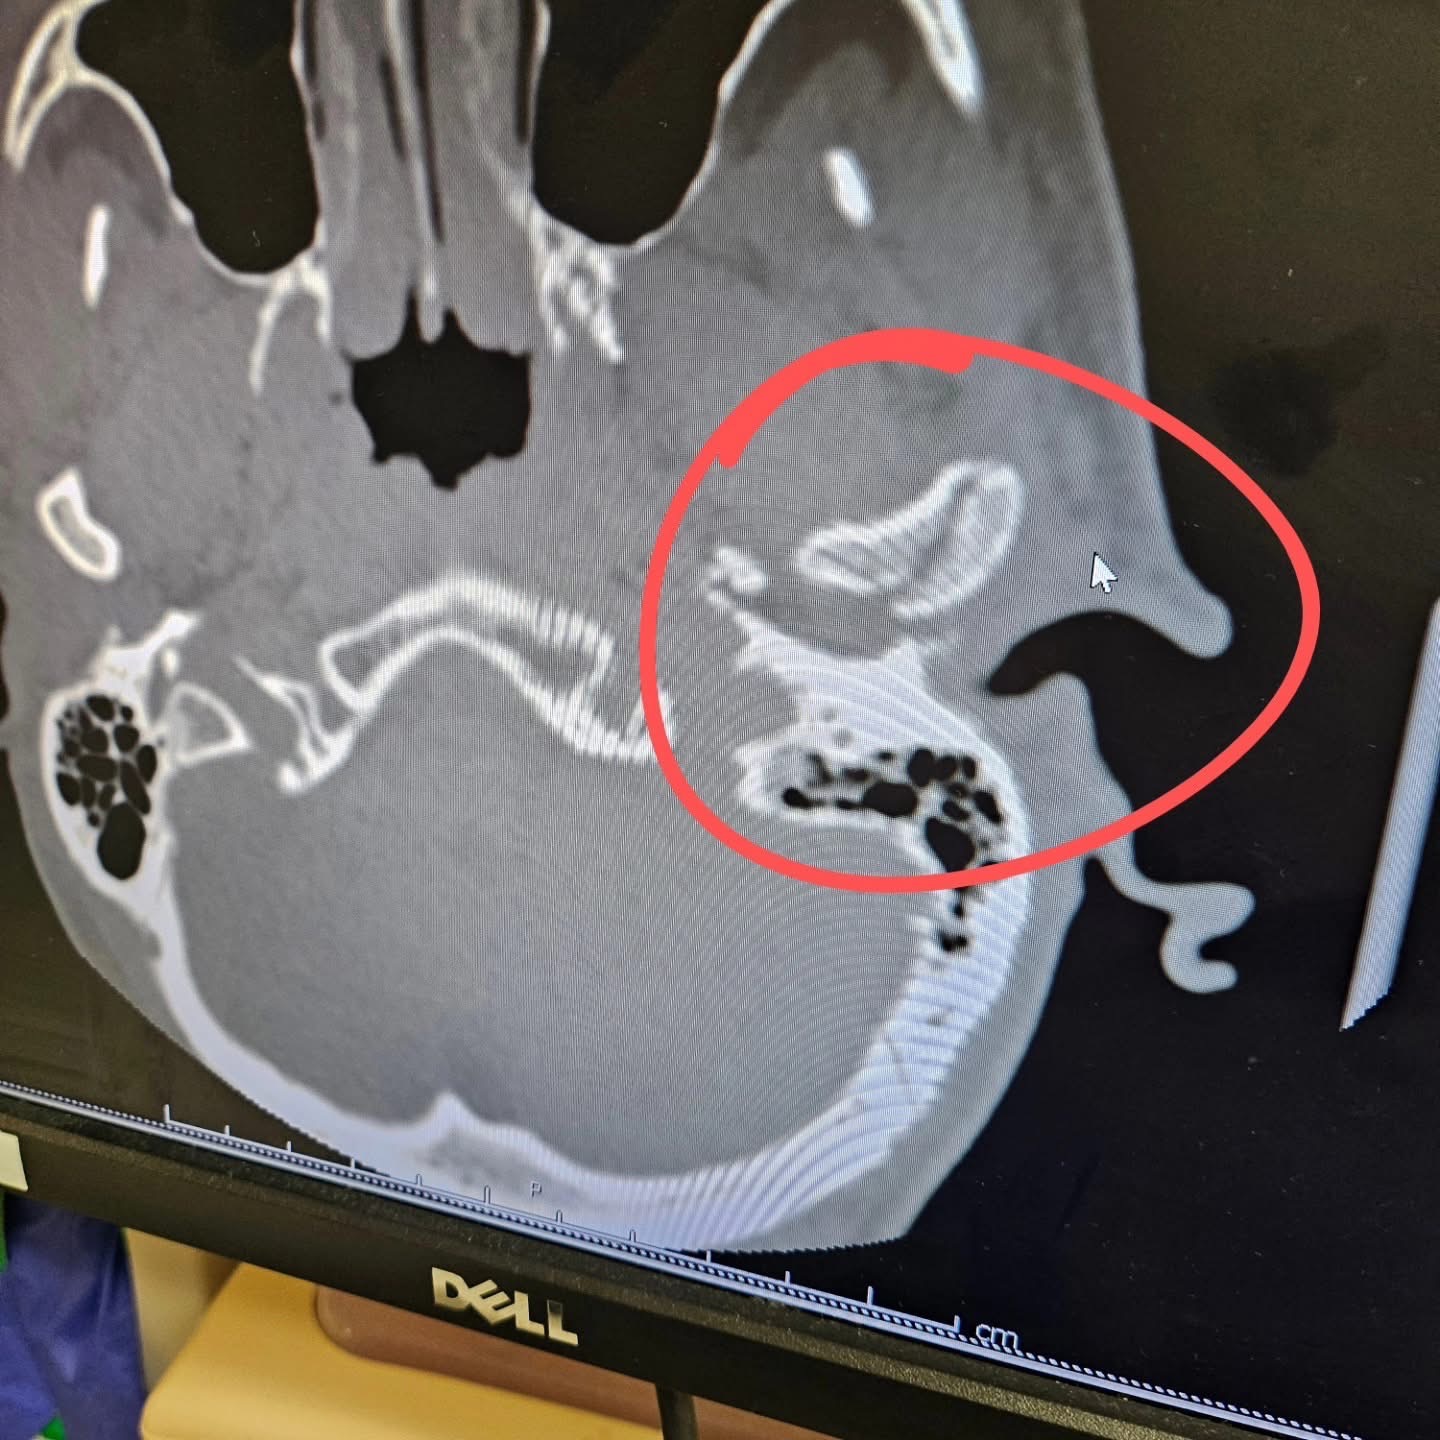

He sustained an injury to his head, a concussion and a broken jaw. A CT scan revealed that part of the jaw fracture is pressing into his ear canal, which has also caused bleeding from his ear.